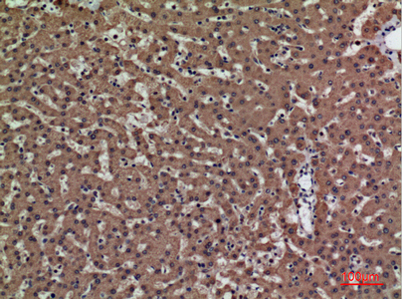

| Dilutions: | Western Blot: 1/500 - 1/2000. IHC-p: 1:100-300 ELISA: 1/20000. Not yet tested in other applications. |